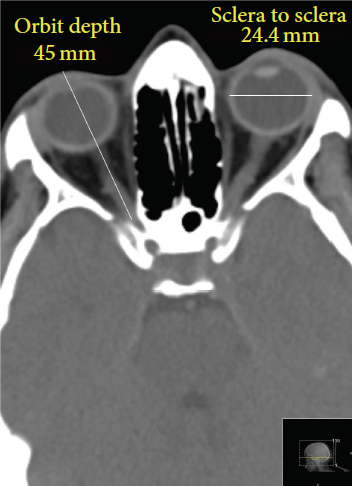

眼球不是一個標準的球形,成年人正常眼球的平均尺寸是:左右寬24.2毫米、上下高23.7毫米、前後長22.0~24.8毫米。大多數人都接近這個尺寸,不過正常眼球的寬度最大可以相差6毫米(21~27毫米)。所以,確實有一些人的眼球比另一些人的更大。

眼球的CT照片 | 圖源:Bekerman, I., Gottlieb, P., & Vaiman, M. (2014)